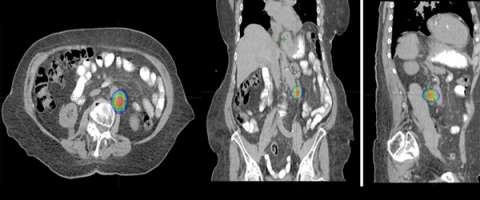

Stereotactic Body Radiation Therapy (SBRT) is a treatment procedure similar to central nervous system (CNS) stereotactic radiosurgery, except that it deals with tumors outside of the CNS. A stereotactic radiation treatment for the body means that a specially designed coordinate-system is used for the exact localization of the tumors in the body (Figure 1) in order to treat it with limited but highly precise treatment fields. SBRT involves the delivery of a single high dose radiation treatment or a few fractionated radiation treatments (usually up to 5 treatments). A high potent biological dose of radiation is delivered to the tumor, improving the cure rates for the tumor, in a manner previously not achievable by standard conventional radiation therapy (Figure 2).

The second row shows images (axial, coronal, and sagittal) of the distribution of the radiation dose that was delivered to this area. One can see that the dose of radiation to this target is very tightly distributed to avoid as much normal tissue as possible.